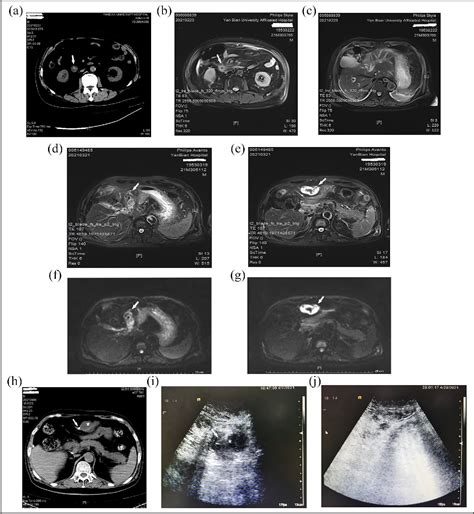

Diagnostic Techniques for Evaluating the Ligamentum Teres Hepatis

Diagnosing conditions related to the ligamentum teres hepatis often involves a combination of imaging techniques and clinical assessments. These methods help to visualize the ligament and surrounding structures, providing valuable information for diagnosis and treatment planning.

Ultrasound

Ultrasound is a non-invasive imaging technique that uses sound waves to create images of internal structures. It is often the first-line diagnostic tool for evaluating the liver and ligamentum teres hepatis. Ultrasound can detect:

• Thrombosis: Blood clots within the ligamentum teres hepatis can be visualized using ultrasound.

• Inflammation: Inflammation of the ligamentum teres hepatis can be detected through changes in tissue texture and blood flow.

• Tumors: Masses or tumors within or near the ligamentum teres hepatis can be identified using ultrasound.

Computed Tomography (CT) Scan

CT scans provide detailed cross-sectional images of the body, allowing for a more comprehensive evaluation of the ligamentum teres hepatis and surrounding structures. CT scans can detect:

• Anatomical Abnormalities: Structural abnormalities of the ligamentum teres hepatis can be visualized.

• Tumors: Detailed images of tumors within or near the ligamentum teres hepatis can be obtained.

• Inflammation: Inflammatory changes in the ligamentum teres hepatis can be detected.

Magnetic Resonance Imaging (MRI)

MRI uses magnetic fields and radio waves to create detailed images of internal structures. It is particularly useful for evaluating soft tissues and can provide valuable information about the ligamentum teres hepatis. MRI can detect: